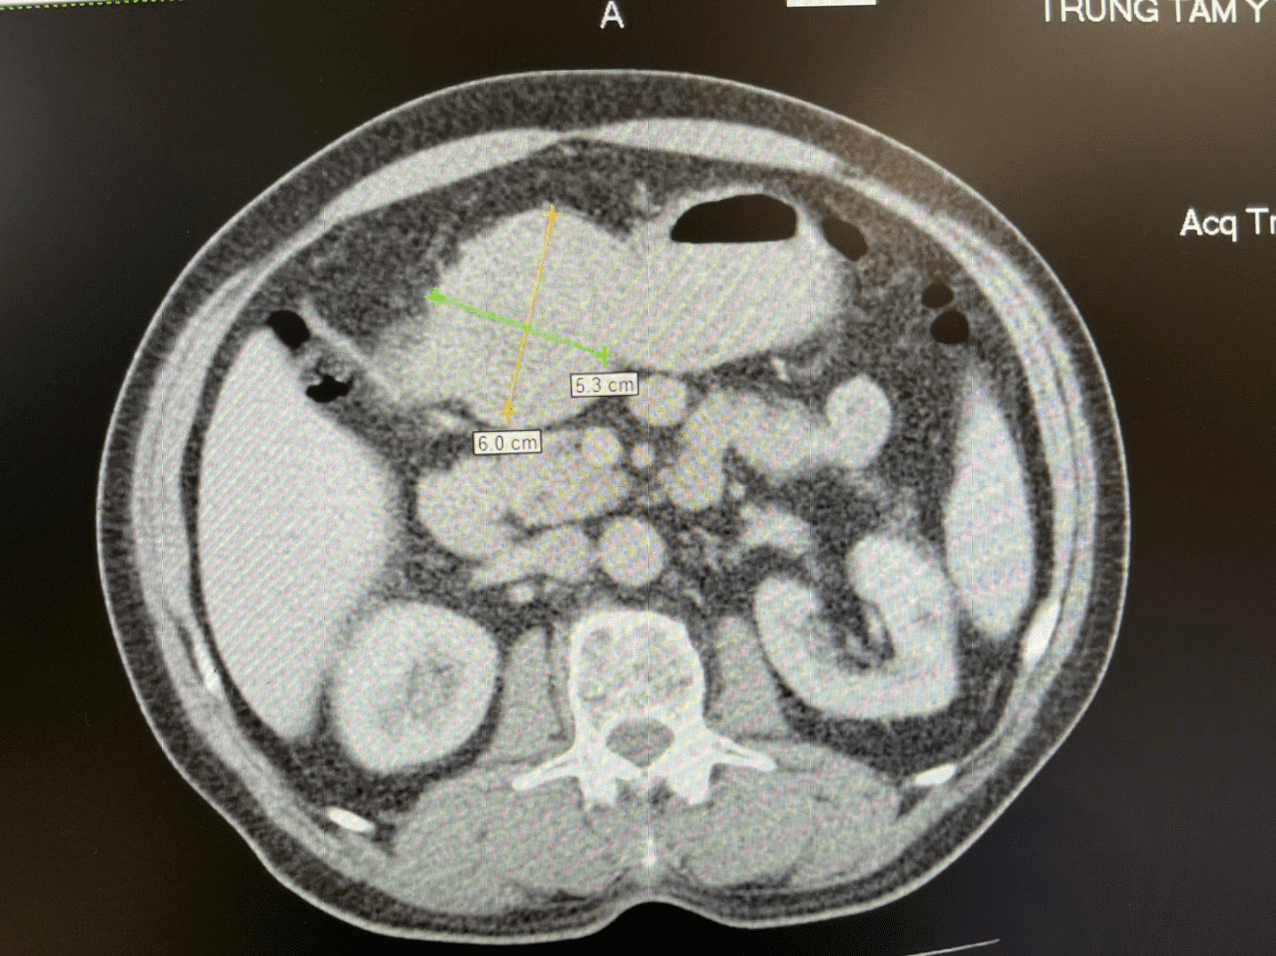

Bệnh nhân Tạ V.S (nam, 71 tuổi), có tiền sử hẹp mạch vành cách đây 8 năm, nhiễm Covid-19 cách đây 3 tháng, một tuần trước khi vào viện bệnh nhân xuất hiện đau bụng thượng vị, đầy hơi, đau tức ngực trái. Khám tại Trung tâm Y tế thành phố Móng Cái, qua kết quả nội soi, siêu âm và chụp cắt lớp vi tính ổ bụng của bệnh nhân phát hiện khối bất thường kích thước 6cm - 5.3cm trong dạ dày. Các bác sĩ đã hội chẩn và chẩn đoán U GIST dạ dày. Bệnh nhân được chỉ định phẫu thuật mổ cắt U GIST.

Khối U trong dạ dày qua hình ảnh chụp cắt lớp vi tính